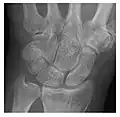

High-energy trauma fractures

Figure 3: A 26-year-old man presenting with wrist pain after being assaulted. (a) Initial anteroposterior radiograph shows a subtle linear lucency within the scaphoid extending to the scaphocapitate articular surface that was overlooked (arrow). (b) Initial "scaphoid" view was negative. (c) Followup anteroposterior radiographs, 12 days later, shows obvious scaphoid fracture (arrows).[1]